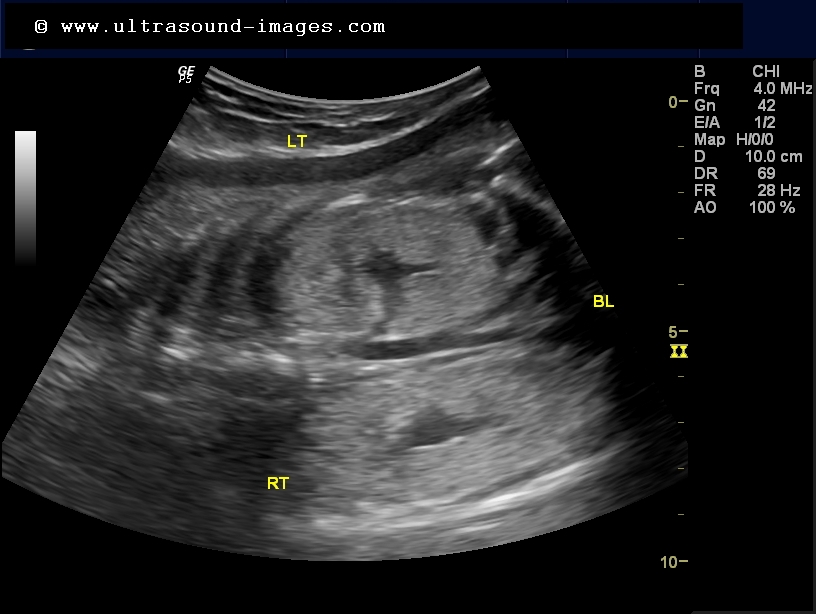

The signs of illness in your cat reflect the failure of the kidneys to do their many jobs well enough. With ultrasound, the doctor can see the baby�s internal organs, including the kidneys and urinary bladder. Kidney problems that are sometimes diagnosed in developing fetuses include polycystic kidney disease, hydronephrosis and fetal multicystic dysplastic kidney. If your baby has hydronephrosis, after she is born, there will probably be further testing. Occasionally, an abnormality is detected in the developing urinary tract.

Doctors can see it on ultrasound sometime by the 12 th week in a pregnancy. My right kidney has hydronephrosis from the pregnancy and little one�s kidneys are also enlarged (although still within normal range). Has anyone else been told that their baby has enlarged kidney? An enlarged kidney is a condition in which a kidney is larger than its normal size. Doctors can see it on ultrasound sometime by the 12 th week in a pregnancy.

Once the baby is born, ultrasound can be used to view the baby�s urinary tract directly for a clearer image than could be achieved while the baby was in the womb. The results will determine when and if further action needs to be taken. Polycystic kidney disease causes cysts to grow in the kidneys. An enlarged kidney can only be felt occasionally during an examination, usually when the patient is an infant, a child or a thin adult, according to the merck. The symptoms associated with an enlarged kidney closely resemble symptoms of several serious medical conditions.

An enlarged kidney in fetus happens when a kidney fills up with fluid. Pyelectasis also is known as renal pelvic dilatation. I had my 32 week growth scan 2 weeks ago and the doctor told me yesterday that one of the kidney�s is enlarged. Different imaging techniques are available to determine the cause of the problem. The baby will continue to be monitored with ultrasound scans and other tests after the birth.